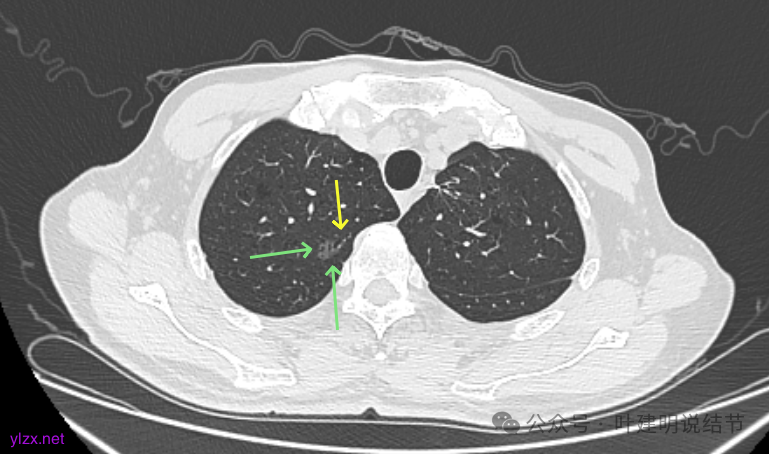

最后看2025年3月的连续层面的影像细节:

右上病灶淡磨密度,有空泡征,整体轮廓较清。

瘤肺边界清楚,空泡征明显。

表面不平,没有实性成分。灶内空泡有些像蜂窝状。

病灶边上有小血管走行,整体轮廓清,没有明显实性成分。

右上病灶淡而纯主要原因,空泡征明显。

左上病灶淡而纯,有微小血管进入。

右上淡磨,轮廓清,空泡明显。

左上的小而局部有细支气管扩张的样子,部分边缘显毛糙,有细毛刺样征。

右上叶病灶有血管贴边,轮廓清;

左上病灶纯磨,轮廓清。

右上淡磨,左下密度较右侧的稍不均一点。